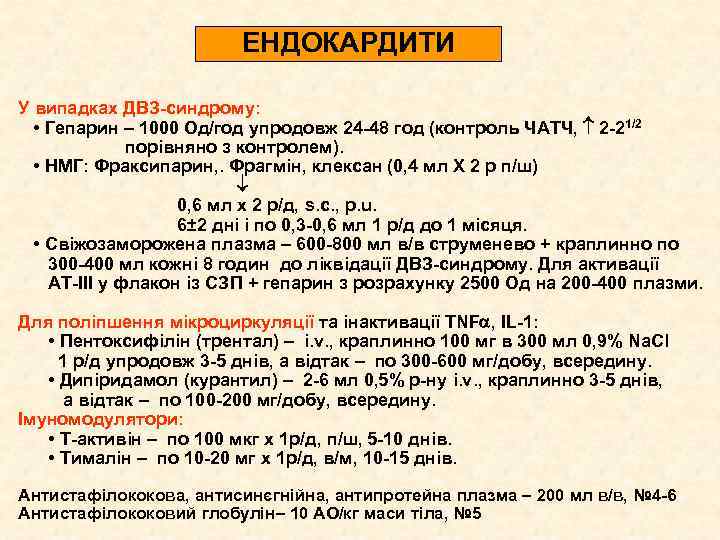

ЕНДОКАРДИТИ У випадках ДВЗ-синдрому: • Гепарин – 1000 Од/год упродовж 24 -48 год (контроль ЧАТЧ, 2 -21/2 порівняно з контролем). • НМГ: Фраксипарин, . Фрагмін, клексан (0, 4 мл Х 2 р п/ш) 0, 6 мл х 2 р/д, s. c. , p. u. 6± 2 дні і по 0, 3 -0, 6 мл 1 р/д до 1 місяця. • Свіжозаморожена плазма – 600 -800 мл в/в струменево + краплинно по 300 -400 мл кожні 8 годин до ліквідації ДВЗ-синдрому. Для активації АТ-ІІІ у флакон із СЗП + гепарин з розрахунку 2500 Од на 200 -400 плазми. Для поліпшення мікроциркуляції та інактивації TNF , IL-1: • Пентоксифілін (трентал) – i. v. , краплинно 100 мг в 300 мл 0, 9% Na. Cl 1 р/д упродовж 3 -5 днів, а відтак – по 300 -600 мг/добу, всередину. • Дипіридамол (курантил) – 2 -6 мл 0, 5% р-ну i. v. , краплинно 3 -5 днів, а відтак – по 100 -200 мг/добу, всередину. Імуномодулятори: • Т-активін – по 100 мкг х 1 р/д, п/ш, 5 -10 днів. • Тималін – по 10 -20 мг х 1 р/д, в/м, 10 -15 днів. Антистафілококова, антисинєгнійна, антипротейна плазма – 200 мл в/в, № 4 -6 Антистафілококовий глобулін– 10 АО/кг маси тіла, № 5